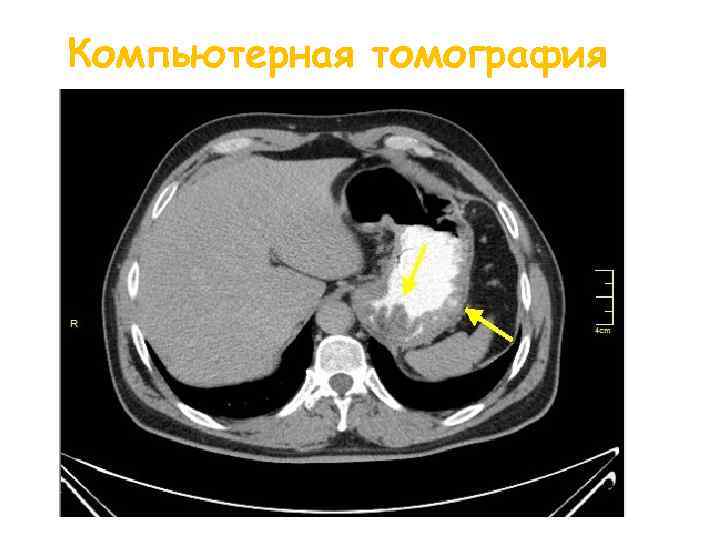

Диагностика Анализ крови Биохимический анализ крови Рентген желудка Эндоскопическое исследование р. Н-метрия КТ

Компьютерная томография